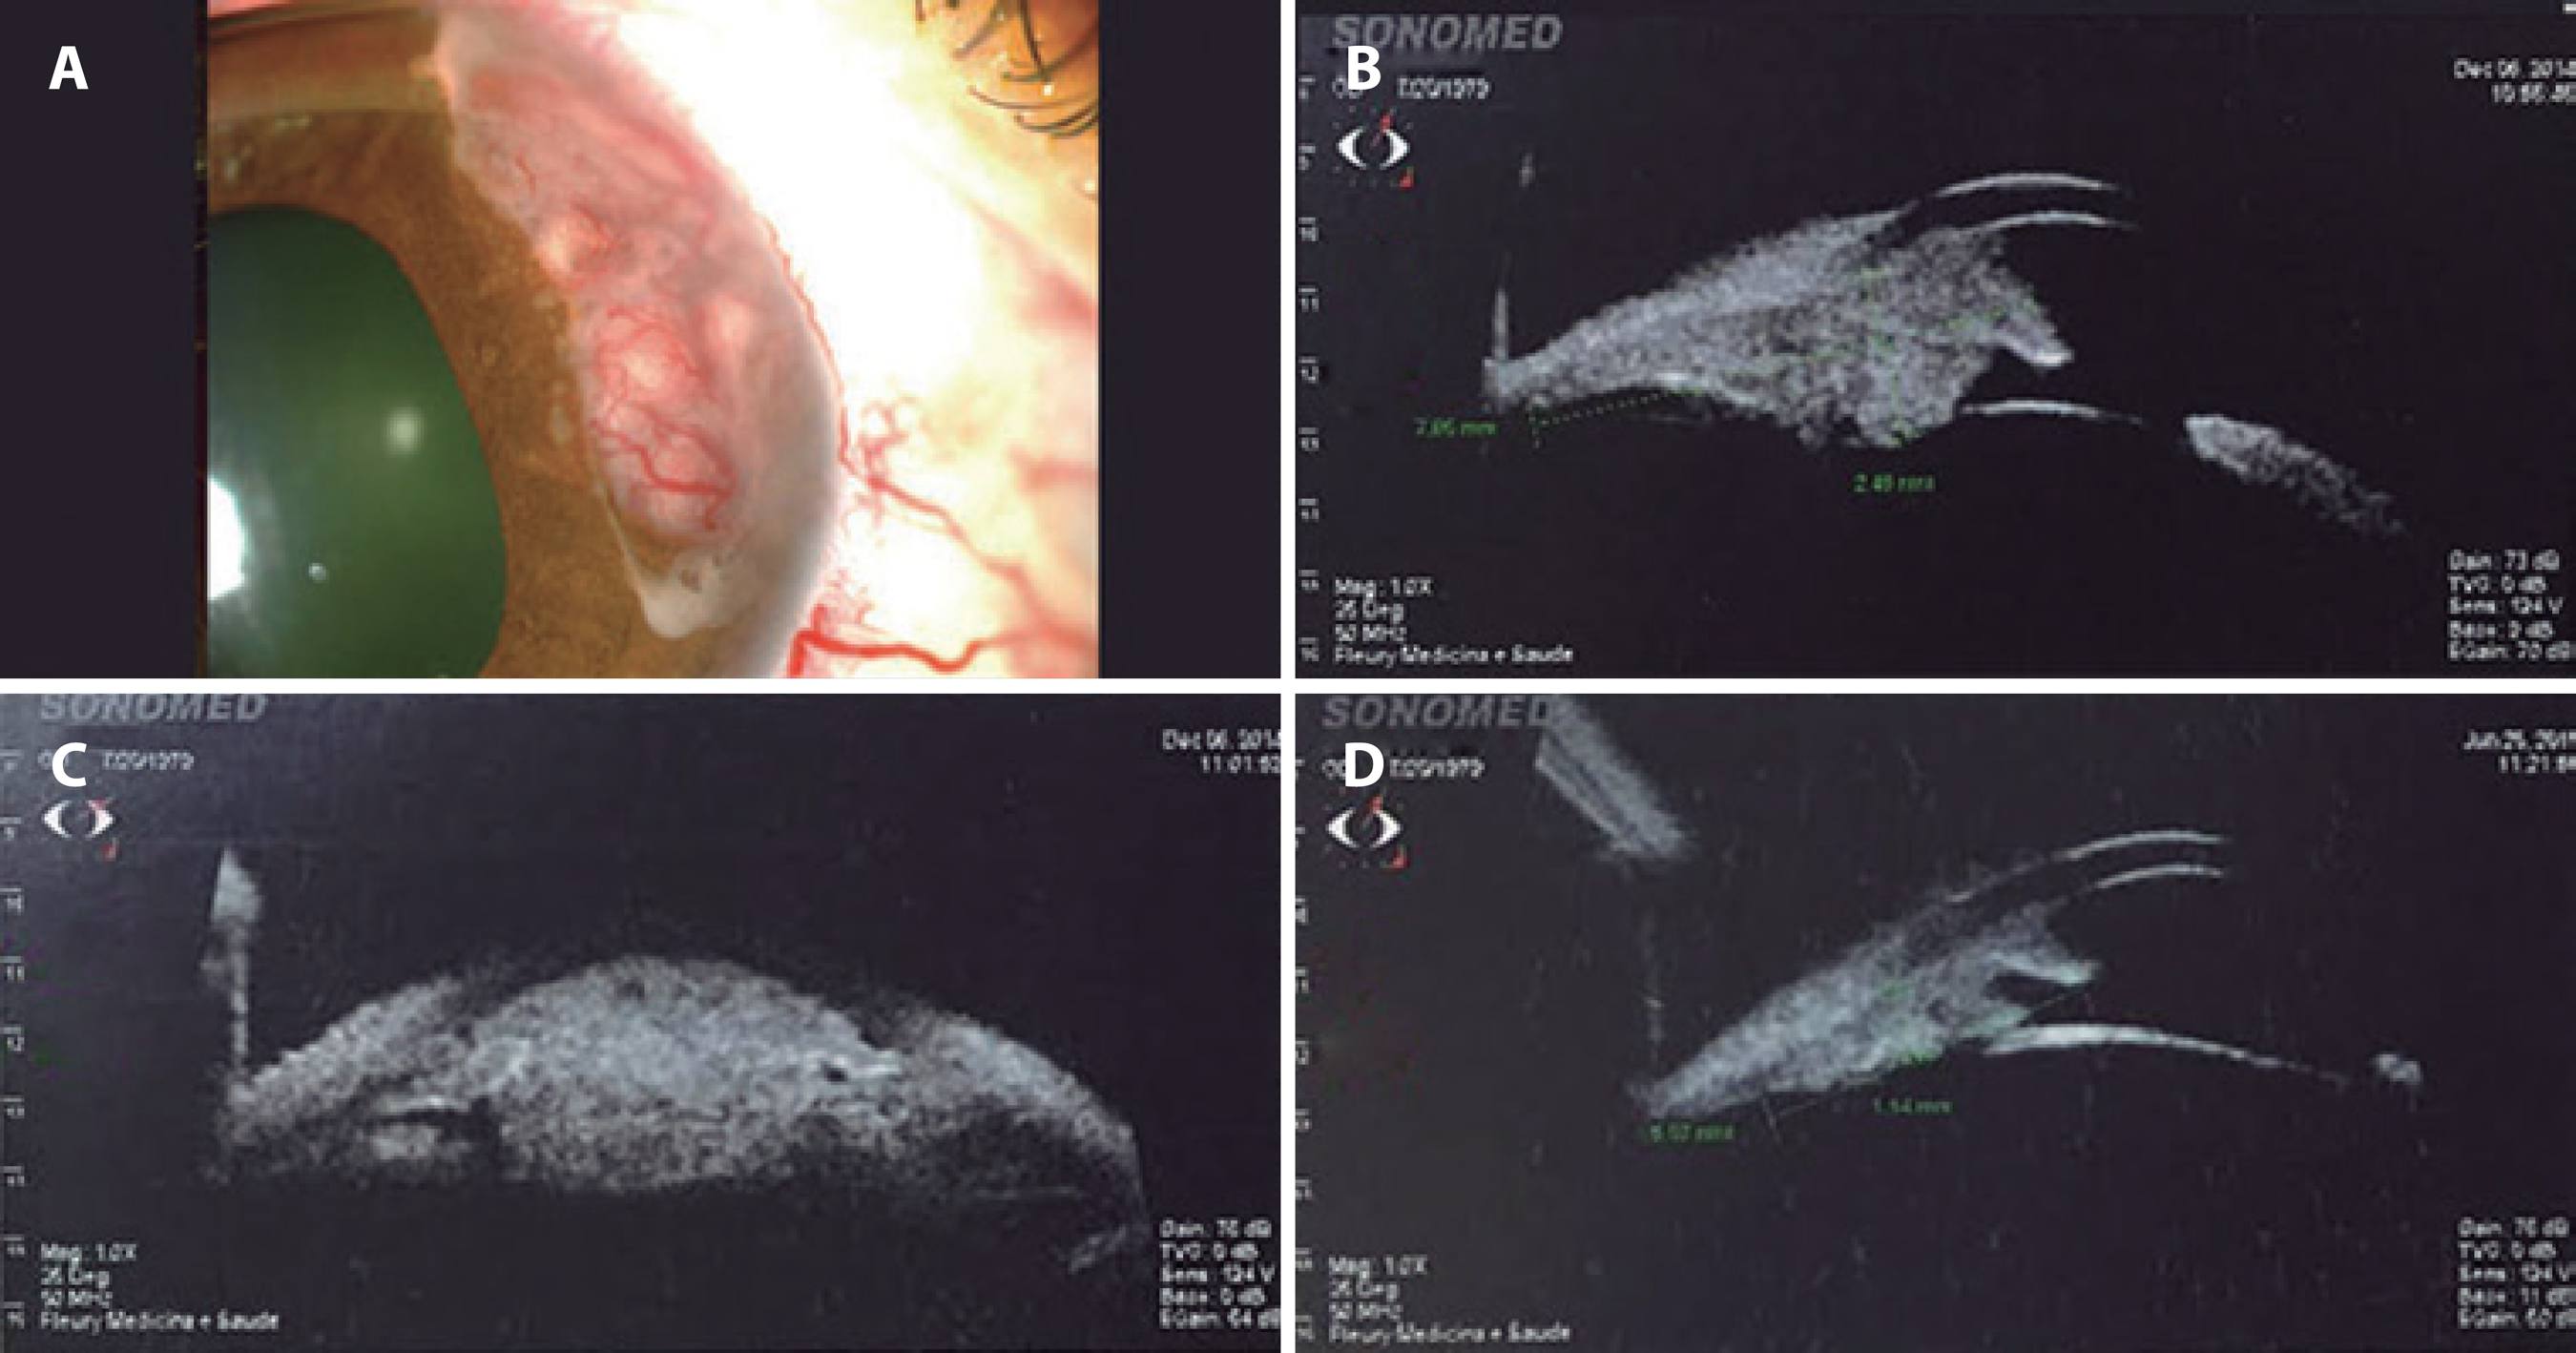

On admission, ocular examination revealed a best-corrected vision of 20/30 in the right eye and 20/20 in the left eye. Full extraocular motion was observed. The pupils were 3 mm in diameter and reactive to light. The right pupil had an area of irregularity inferiorly, and there were neovessels in the collarette (Figure 1 A). A 2+/4+ anterior chamber reaction with no keratic precipitates were also observed. Further, a 7 × 4 mm pinkish-yellow mass from 1 to 5 o'clock with intrinsic friable vessels was observed, in addition to a band of tissue from 7 to 9 o'clock in the anterior chamber. The intraocular pressure was 25 mmHg (right eye) and 12 mmHg (left eye), as determined by applanation tonometry. Fundoscopic examination was normal. Based on all these findings, a clinical diagnosis of an iris tumor was made. Ultrasound biomicroscopy (UBM) of the right eye revealed an iridociliary mass with homogeneous reflectivity, featuring areas of internal hyporeflective spaces within the tumor with clear margins (Figure 1 B). UBM of the left eye was normal.

Hypotensive agents and topical prednisolone 1% three times daily were initiated. Magnetic resonance imaging (MRI) revealed a renal mass, in addition to liver, brain, and pulmonary masses. A clinical diagnosis of iridociliary metastasis arising from a primary renal carcinoma was established. Treatment with oral anti-tyrosinase was initiated, leading to shrinkage of both the iris and the systemic lesions (Figures 1 C and 1 D). The patient remains alive at 18 months after the initial diagnosis.

Figure 1 Case 1. A) Photography demonstrating a 7 × 4-mm pinkish-yellow mass from 1 to 5 o'clock with intrinsic friable vessels. A band of tissue was observed from 7 to 9 o'clock in the anterior chamber. B) Ultrasound biomicroscopy (UBM) image of an iridociliary mass with homogeneous reflectivity and areas of internal hyporeflective spaces within the tumor. C and D) Post-treatment images demonstrating shrinkage of the lesion.